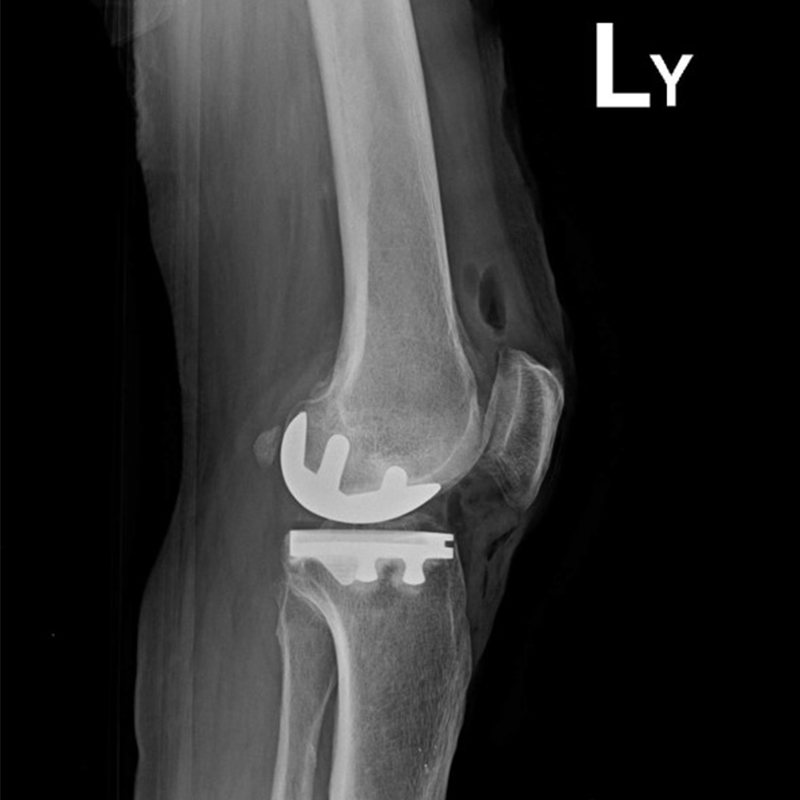

傳統部分膝置換 首頁 案例分享 膝關節手術 傳統部分膝置換 殷女士 65歲 術前 術後 張女士 71歲 術前 術後 蔡女士 74歲 術前 術後 張女士71歲 術前 術後 翁女士70歲 術前 術後 劉女士 80歲 術前 術後